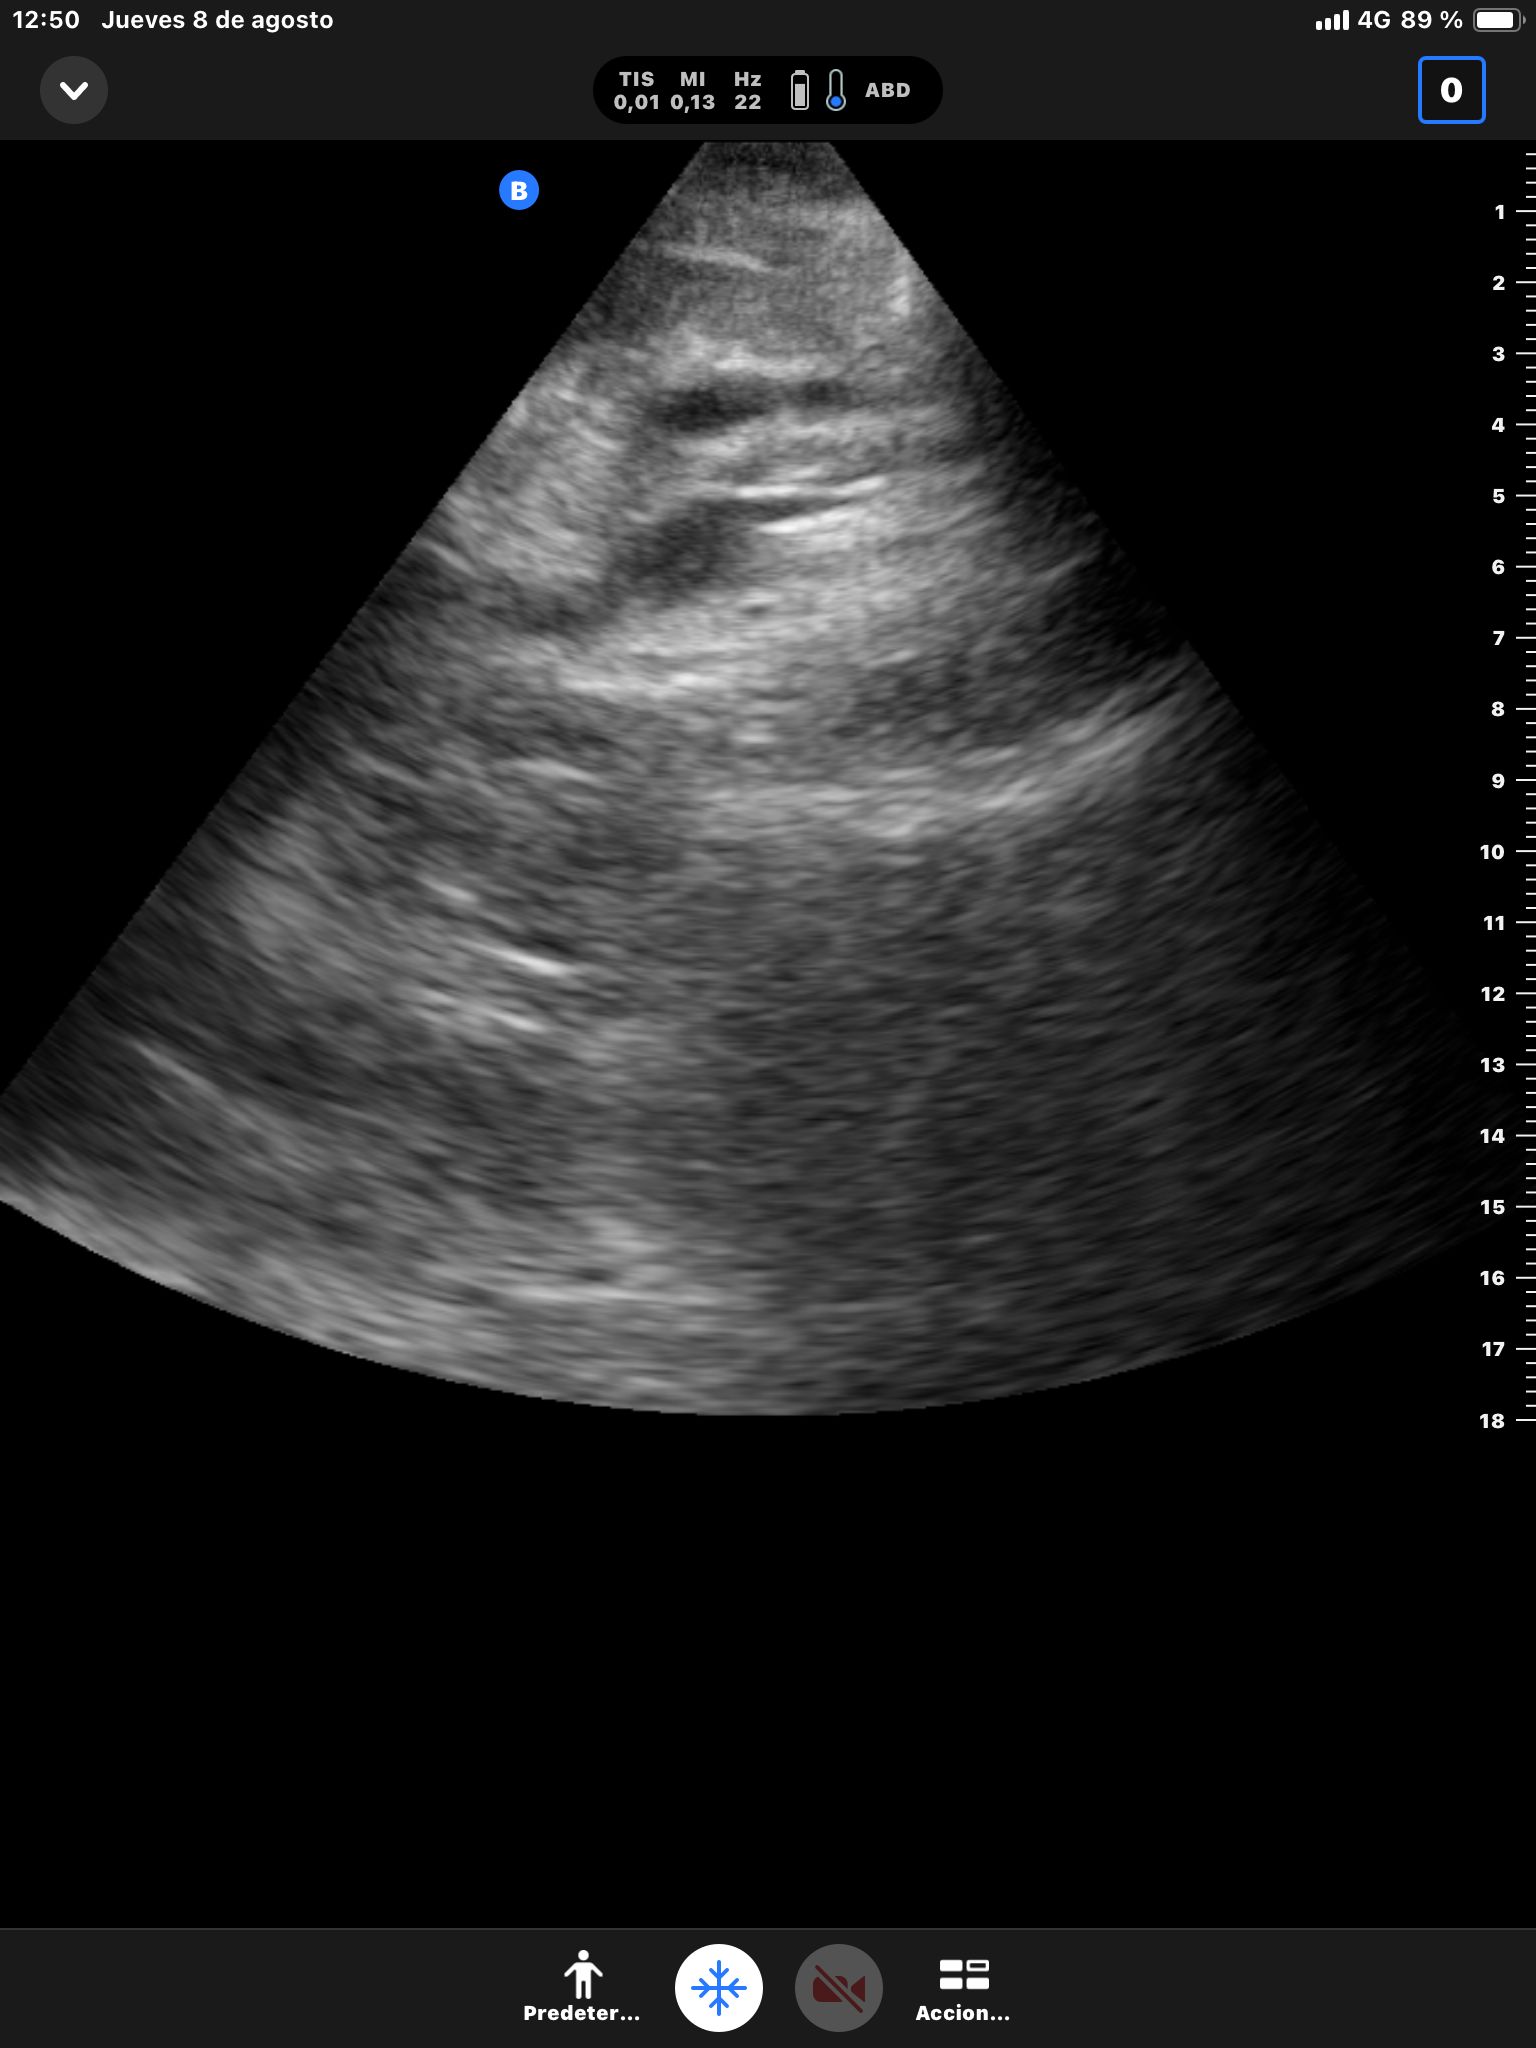

Se realiza ecografía abdominal.

Descripción de los hallazgos ecográficos y las imágenes más relevantes para la resolución del caso

Hígado sin LOEs. Vesícula biliar con hidrops (58 mm), dilatación del colédoco (10 mm). Páncreas hiperecogénico, atrófico, Wirsung de 76 mm.